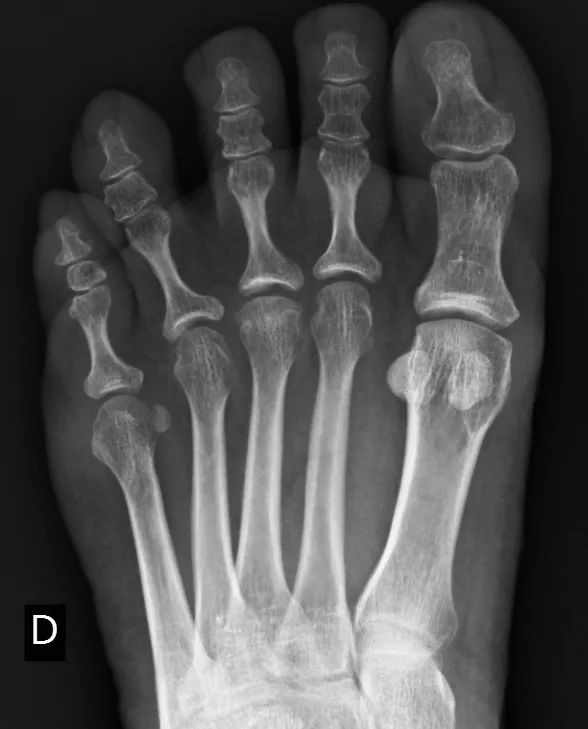

CASE F40 类风湿关节炎患者

第三右跖骨头结构的轻度改变,扁平,有一条细微的硬化线,提示有骨坏死。